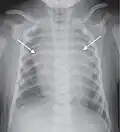

A normal posteroanterior (PA) chest radiograph of someone without any signs of injury. Dx and Sin stand for "right" and "left" respectively.